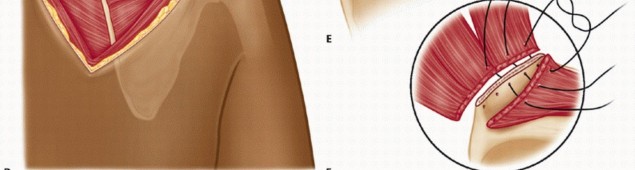

The initial “safe” portal is placed at the level of the scapular spine, just medial to the scapular edge, to avoid injury to the dorsal scapular nerve and artery (TECH FIG 2A).

The scapulothoracic space is localized with a spinal needle and distended with approximately 30 mL of saline, and the portal is created.

A blunt obturator is inserted into the scapulothoracic (subserratus) bursa between the posterior thoracic

wall and the serratus anterior muscle.

Care should be taken to avoid overpenetration through the serratus anterior into the subscapular space or through the chest wall.

A 30-degree arthroscope is inserted into the scapulothoracic space, which was distended with fluid infiltration.

Use of a fluid pump is optional. Our preference is to use an arthroscopy pump, but keep the pressure low, at around 30 mm Hg, to minimize fluid extravasation.

A spinal needle is used to localize the second portal under direct visualization.

This portal is inserted, in most instances, in line with and approximately 4 cm distal to the first portal.

The initial “safe” portal is placed at the level of the scapular spine, just medial to the scapular edge, to avoid injury to the dorsal scapular nerve and artery (TECH FIG 2A).

The scapulothoracic space is localized with a spinal needle and distended with approximately 30 mL of saline, and the portal is created.

A blunt obturator is inserted into the scapulothoracic (subserratus) bursa between the posterior thoracic

wall and the serratus anterior muscle.

Care should be taken to avoid overpenetration through the serratus anterior into the subscapular space or through the chest wall.

A 30-degree arthroscope is inserted into the scapulothoracic space, which was distended with fluid infiltration.

Use of a fluid pump is optional. Our preference is to use an arthroscopy pump, but keep the pressure low, at around 30 mm Hg, to minimize fluid extravasation.

A spinal needle is used to localize the second portal under direct visualization.

This portal is inserted, in most instances, in line with and approximately 4 cm distal to the first portal.

TECH FIG 2 • A. Locations of the arthroscopic portals. A proximal (safe) portal (black arrow) is placed just medial to the spine of the scapula. A distal portal (white arrow) is placed in line with and 4 cm distal to the proximal portal. B. Sites of portal placement. The shaver and the camera can be placed interchangeably in either portal for viewing and shaving.

Alternatively, a superior scapular portal (Bell portal) may be developed as a working portal.7 The superior portal is localized between the medial and middle third of the scapula. The authors do not routinely use this portal due to its proximity and theoretical risk of injury to the spinal accessory, long thoracic, and suprascapular nerves.

A bipolar radiofrequency device and a motorized shaver are introduced into a 6-mm cannula through the lower portal and used to resect the bursal tissue. Because the inflamed scapulothoracic bursa is a potential source of bleeding during arthroscopic shaving, the radiofrequency device becomes particularly useful to minimize bleeding in these tissues (TECH FIG 2B).

A methodic approach to resection should be followed because there are no real landmarks. Ablation of tissues should be performed from medial to lateral and then from inferior to superior.

The surgeon should be ready to switch portals and should have a 70-degree arthroscope ready to facilitate visualization. A probe can be used to palpate the scapula and serratus muscle superiorly and the ribs and intercostal muscles inferiorly.

An additional superior portal may be placed as needed. We prefer not to use this portal because it may

place the accessory spinal nerve, transverse cervical artery, and dorsal scapular neurovascular structures at risk.

After complete bursectomy is performed, the arthroscopic instruments are withdrawn, and skin closure is performed with absorbable subcuticular sutures.

TECH FIG 2 • A. Locations of the arthroscopic portals. A proximal (safe) portal (black arrow) is placed just medial to the spine of the scapula. A distal portal (white arrow) is placed in line with and 4 cm distal to the proximal portal. B. Sites of portal placement. The shaver and the camera can be placed interchangeably in either portal for viewing and shaving.

Alternatively, a superior scapular portal (Bell portal) may be developed as a working portal.7 The superior portal is localized between the medial and middle third of the scapula. The authors do not routinely use this portal due to its proximity and theoretical risk of injury to the spinal accessory, long thoracic, and suprascapular nerves.

A bipolar radiofrequency device and a motorized shaver are introduced into a 6-mm cannula through the lower portal and used to resect the bursal tissue. Because the inflamed scapulothoracic bursa is a potential source of bleeding during arthroscopic shaving, the radiofrequency device becomes particularly useful to minimize bleeding in these tissues (TECH FIG 2B).

A methodic approach to resection should be followed because there are no real landmarks. Ablation of tissues should be performed from medial to lateral and then from inferior to superior.

The surgeon should be ready to switch portals and should have a 70-degree arthroscope ready to facilitate visualization. A probe can be used to palpate the scapula and serratus muscle superiorly and the ribs and intercostal muscles inferiorly.

An additional superior portal may be placed as needed. We prefer not to use this portal because it may

place the accessory spinal nerve, transverse cervical artery, and dorsal scapular neurovascular structures at risk.

After complete bursectomy is performed, the arthroscopic instruments are withdrawn, and skin closure is performed with absorbable subcuticular sutures.